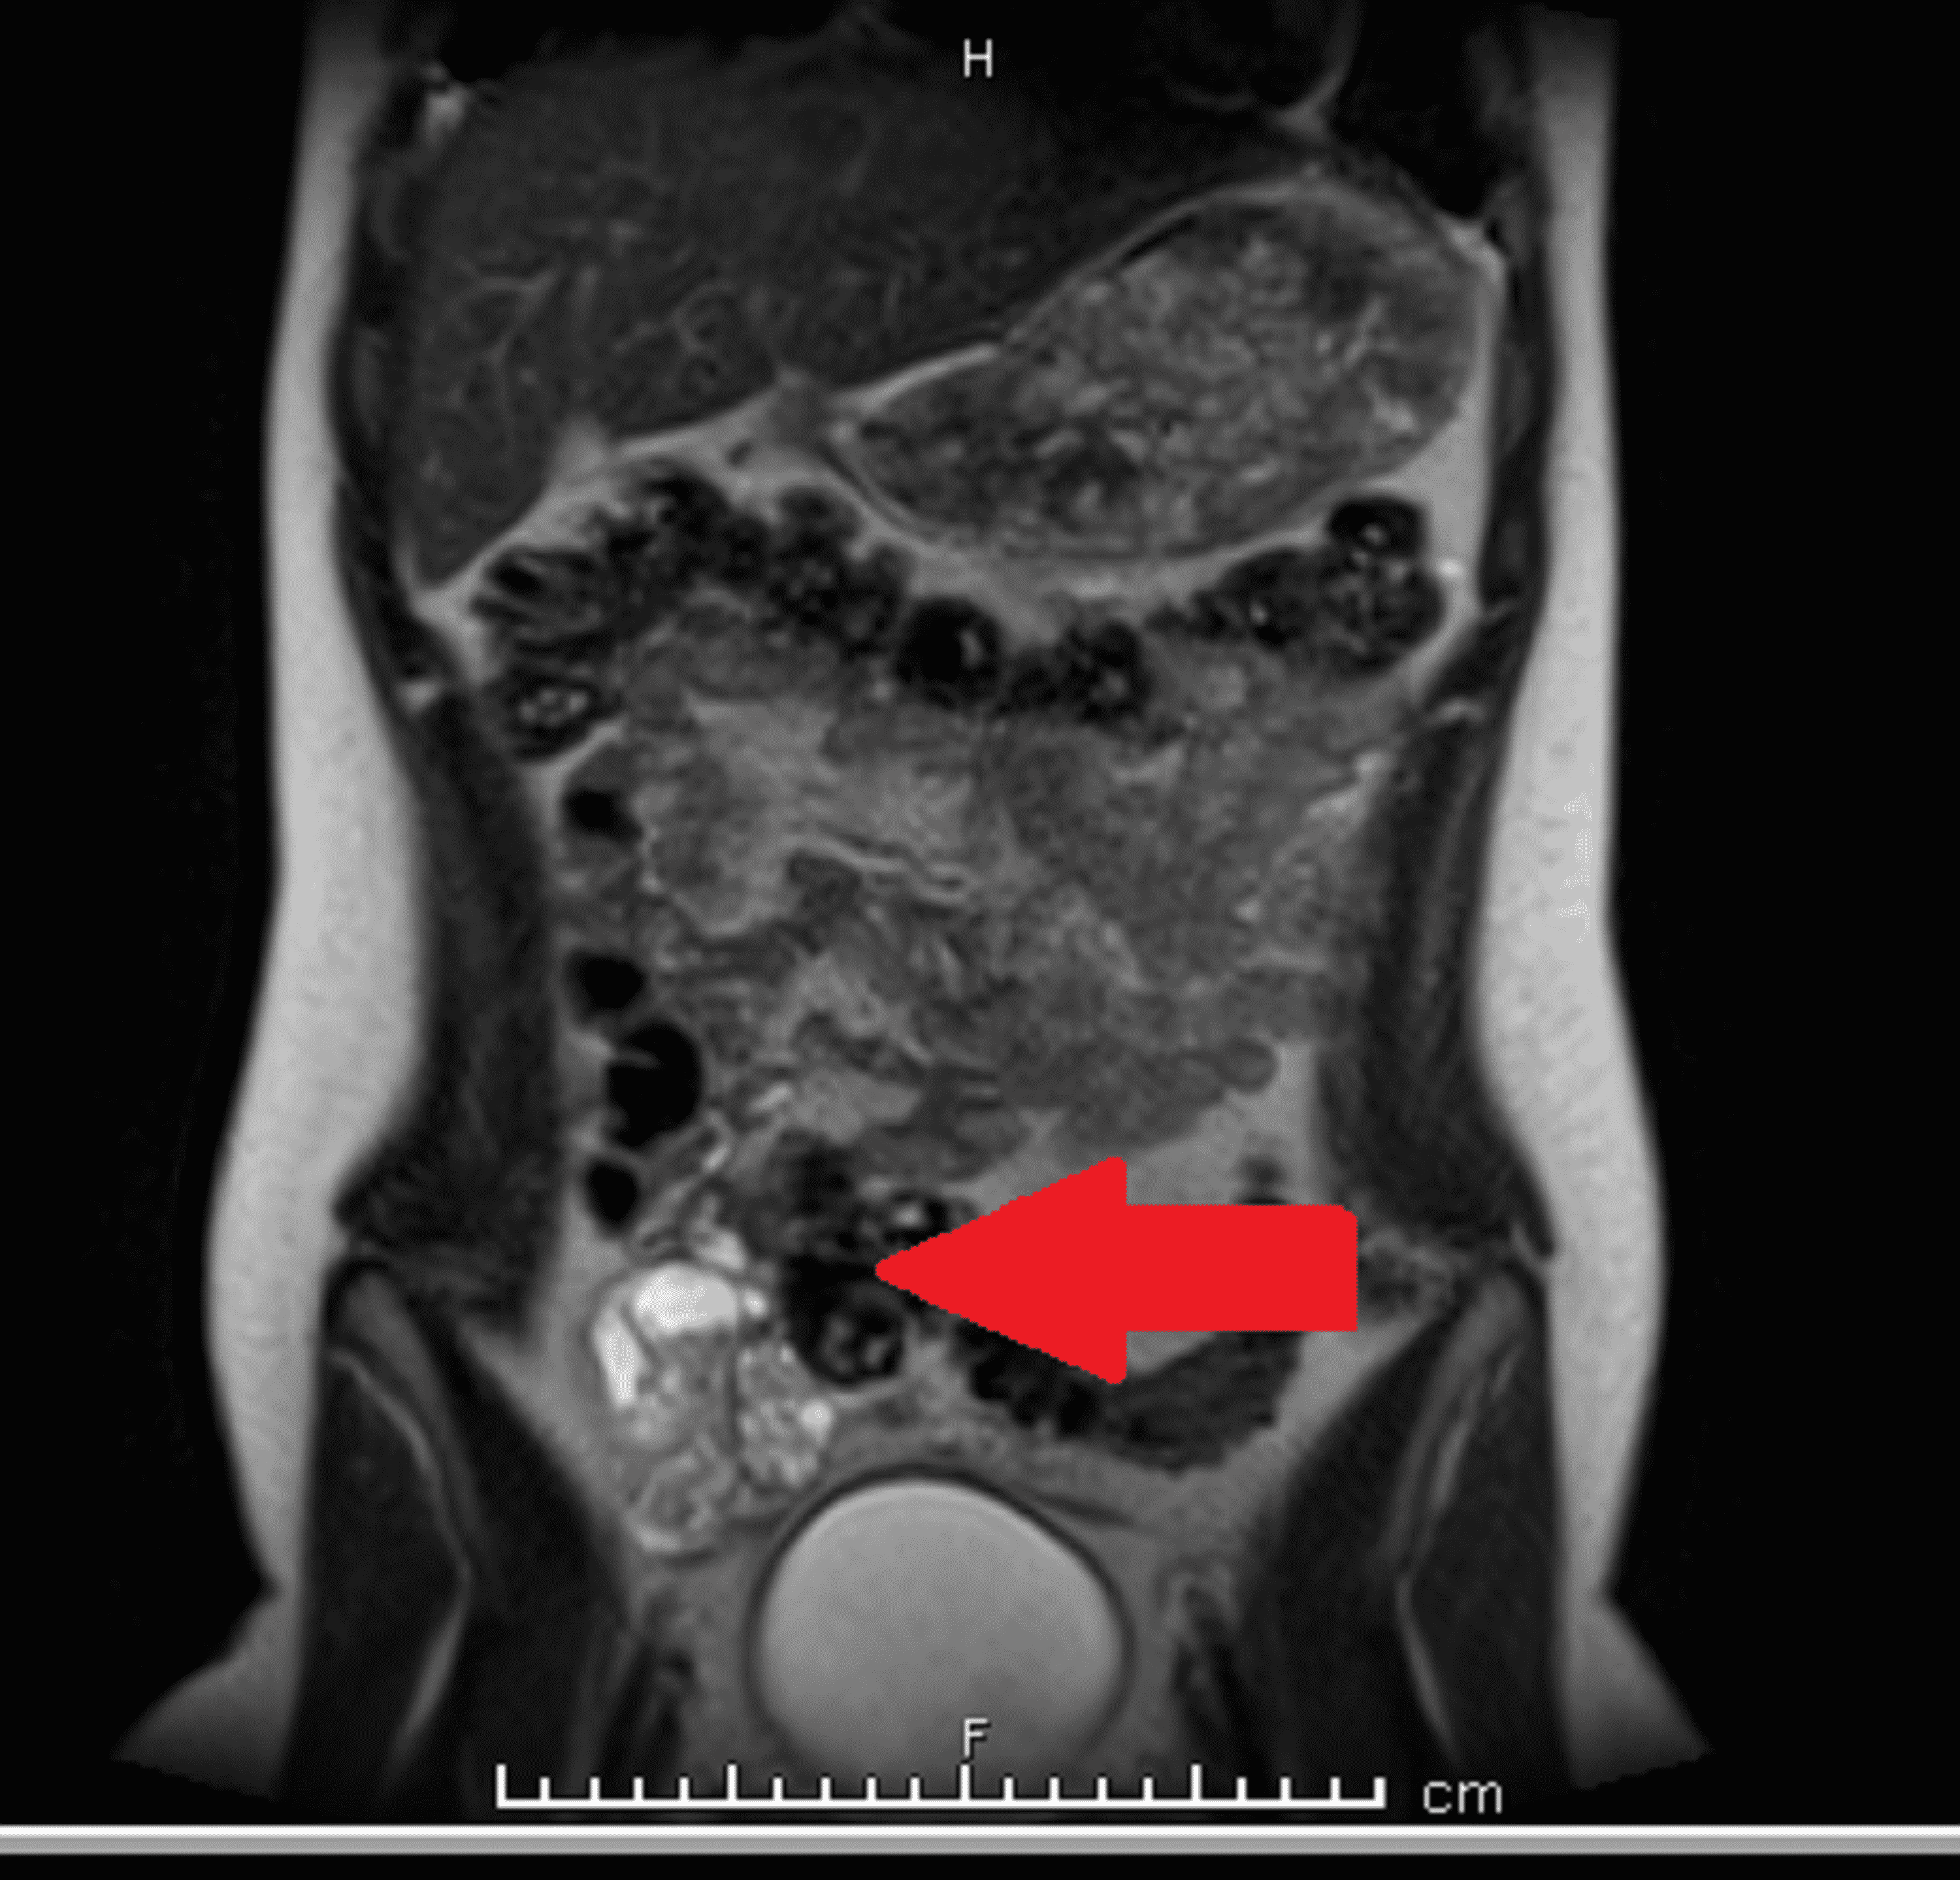

a, Urethral ballooning (arrow) and bladder trabeculation (arrowheads What Is Spinning Top Urethra an anteroposterior image from the voiding phase shows focal dilatation of the posterior urethra between the internal. It is commonly regarded as. spinning top urethra (stu) is a term used to describe a widened posterior urethra seen mainly in girls. It is commonly regarded as. the more common outlet dysfunction is the spinning top urethra. It is. What Is Spinning Top Urethra.